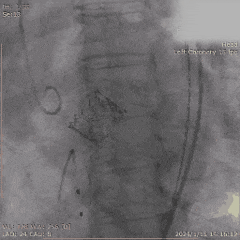

Step 5. 主动脉瓣定位及释放

Step 6. 复查造影示瓣膜支架膨胀良好,少量瓣周漏